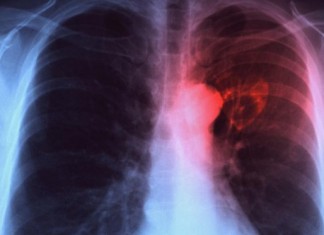

La obsolescencia tecnológica pone en riesgo al paciente con cáncer

La gravedad de la enfermedad admite poco margen de error en los tratamientos

La obsolescencia de la tecnología médica hospitalaria para el cáncer pone en peligro a los enfermos, que dependen de dosis de...